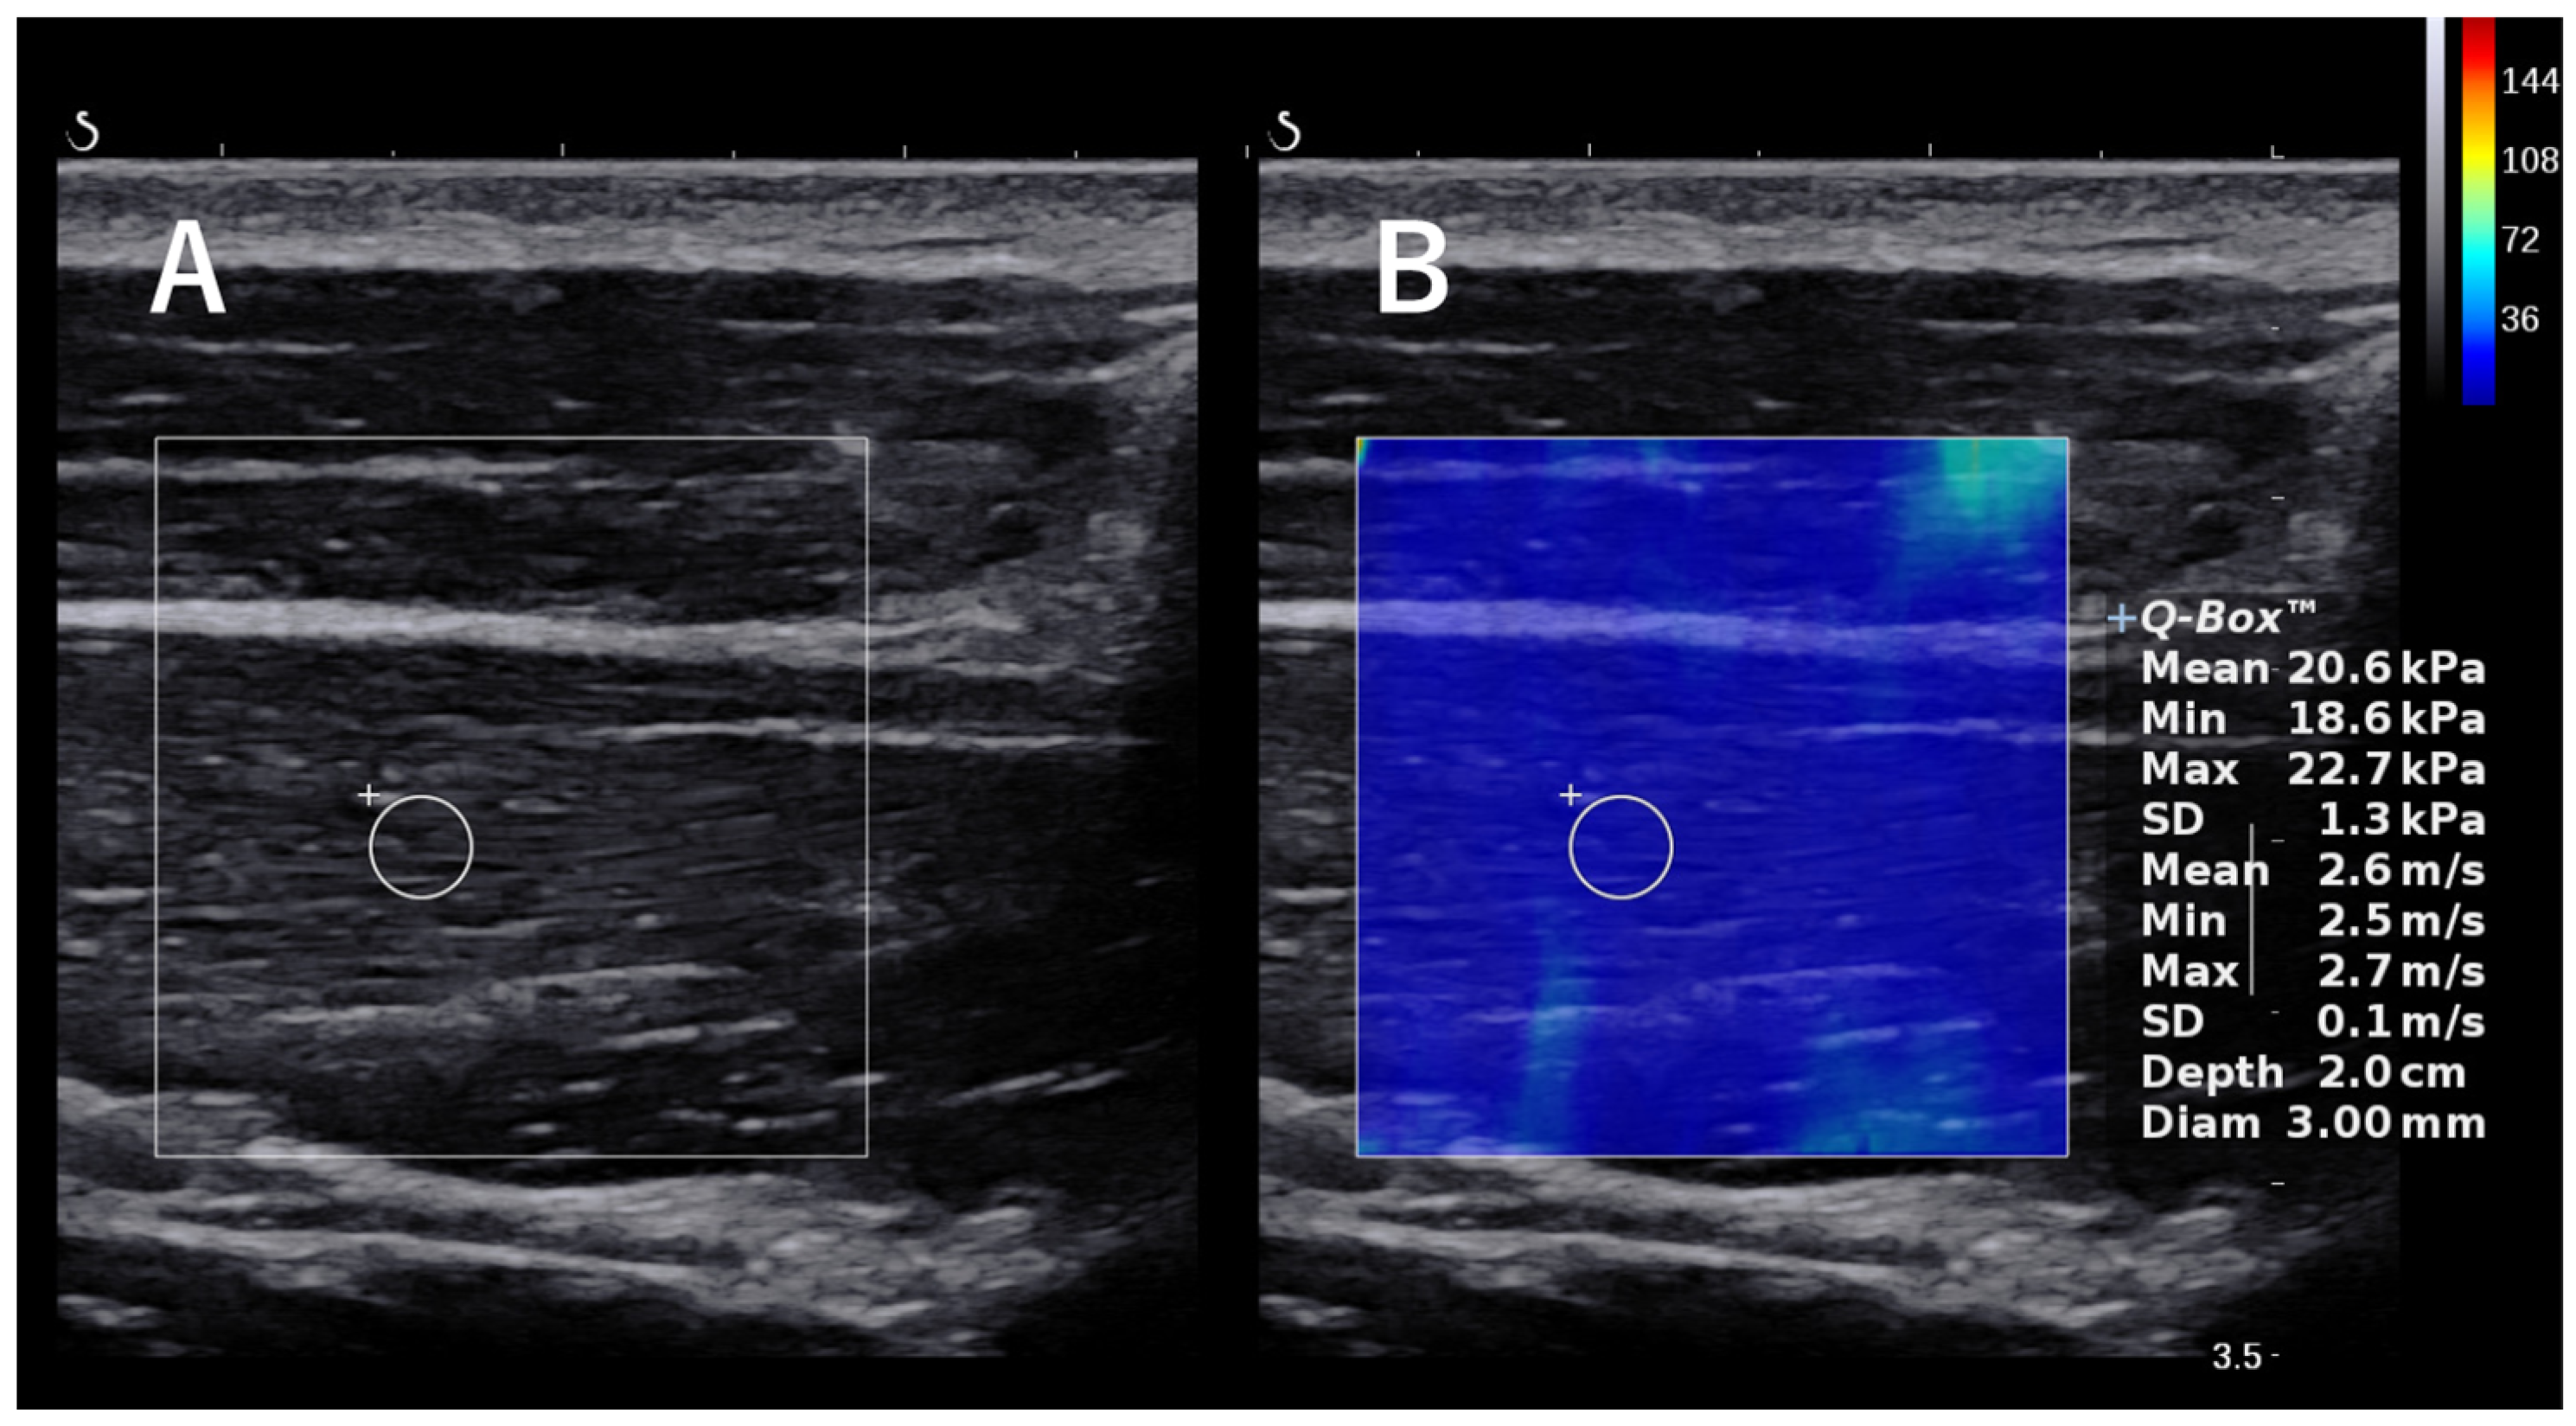

Figure 3.

The images of shear wave elastography. The circle in the figure is the region of interest. (A) B-mode ultrasound image showing the supraspinatus muscle. (B) B-mode image with overlaid elastogram. The circular region of interest was set near the central part of the muscle.

SWE was measured using an Aixplorer (Supersonic Imagine, Aix-en-Provence, France). The examinations were performed by a single shoulder surgeon with 6 years of experience who is experienced with the ultrasound technique. Subjects were examined using SWE to assess the elasticity of muscles and associated components in the shoulder region, including the supraspinatus (SSP) tendon, infraspinatus (ISP) tendon, subscapularis (SSC) tendon, teres minor (TM) tendon, SSP muscle, ISP muscle transverse part, ISP oblique part, TM muscle, lower trapezius (LT) muscle, latissimus dorsi (LD), pectoralis minor (PMi) muscle, posterior capsule, and posteroinferior capsule. When measuring the SSP tendon, ISP tendon, and TM tendons, the participants were scanned in a seated position with the throwing arm relaxed (forearm resting on the ipsilateral thigh) along the tendon. When measuring the SSC tendon, the participants were scanned along the tendon with the upper extremity in a 45° external rotation position with the upper extremity drooped (Figure 2B). When the probe was applied to the supraspinatus fossa, the trapezius muscle was identified in the superficial layer and the SSP muscle was observed beneath it. The ISP transverse and oblique parts were scanned along the muscle fibers positioned 1 cm and 2 cm from the center of the scapular spine, respectively [20]. For the low trapezius muscle, the lateral edge of the transducer was placed 5 cm below the root of the spine of the scapula, and the body of the transducer was inclined at approximately 55° to appear on the long axis of the muscle, as described in a previous study [21]. The LD was scanned by placing the probe parallel to the muscle fibers at three fingerbreadths distal to and along the posterior axillary fold [22]. When the probe was placed medial to the coracoid process, the PMi muscle, which is attached to the coracoid process, was observed beneath the pectoralis major muscle. The measurement site of the PMi was defined as the midpoint between the coracoid process and the fourth rib and sternum junction [23]. The location of the transducer was adjusted to clearly visualize the humeral head, glenoid rim, labrum, and ISP, and the elasticity of the posterior capsule beneath the ISP was measured 5 mm lateral to the edge of the labrum. The location of the transducer was adjusted to clearly visualize the humeral head, glenoid rim, labrum, and TM muscle, and the elasticity of the posteroinferior capsule was measured in the same manner as the measurements of the posterior capsule (i.e., at a location 5 mm lateral to the edge of the labrum) [24]. SWE measurements of the SSP tendons, ISP tendons, TM tendons, and SSC tendons were taken just above the medial border of the tendon attachment. Figure 2 shows the probe placement for each muscle; all muscles were scanned along the long axis, displaying B-mode images. A color-coded box showing the shear elastic modulus was superimposed on the B-mode ultrasound image, and the circular region of interest was set near the central part of the muscle (Figure 3). We performed each measurement twice and used the mean of the two values for the analysis.